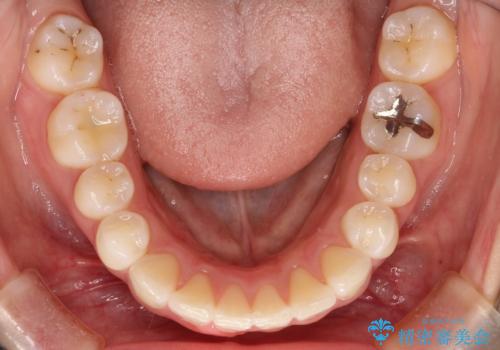

- 前歯のがたつきと出っ歯が気になるとのことで来院されました。

上顎の前から4番目の歯を両側合計2本抜歯して矯正することとなりました。

抜歯をして矯正をすることで、前歯を後方に移動させ、ガタガタを改善することができました。